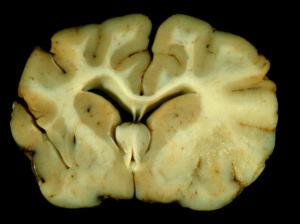

病理檢查

希爾德病主要依據:(1)兒童或青步年發病,亞急性發病逐漸進展病程。(2)智慧型減退,視力下降甚至皮層盲、瘴痛以及精神症狀等表現。(3)影像學示雙側半卵圓中心,以枕葉為主的白質脫鞘改變。(4)長鏈脂肪酸含量正常。(5)排除其它疾病。Cr表現為雙側半球白質廣泛低密度改變=MRI示雙側半球白質長長改變,病灶邊緣界線較清楚,自室營膜下至皮質下,以枕葉為主,雙側可不對稱。率組病例影像學檢查均符合此病的改變,均支持瀰漫性硬化改。